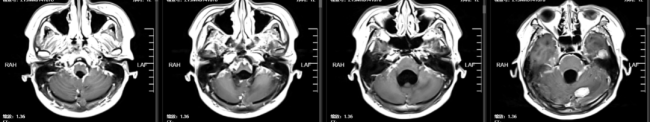

2024年5月18日,患者出现神经系统相关症状,颅脑MR检查提示脑脊髓膜转移。2024年10月29日,患者首次就诊于陶荣杰主任团队的神经肿瘤科。团队结合患者病史、病理特征及脑膜转移的临床特点,制定了全身与局部相整合的治疗方案:采用塞替派全身化疗联合塞替派鞘内注射,以针对性降低脑膜转移的局部肿瘤负荷;同时联用贝伐单抗进行抗血管生成治疗,改善肿瘤微环境并增加血脑屏障通透性;此外,基于患者HR阳性的分子特征,加用达尔西利联合氟维司群(CDK4/6抑制剂联合内分泌靶向治疗),以实现全身肿瘤的综合控制。

2025年3月31日,患者第四次入院,复查颅脑MR提示:脑内、软脑膜、延髓可见多发异常强化,提示多发转移瘤。根据病情变化,团队优化治疗方案,调整为塞替派联合德曲妥珠单抗治疗,以进一步强化靶向治疗效果。2025年6月10日,颅脑MR检查提示病情达到部分缓解(PR),脑膜转移灶较前明显改善,患者临床症状显著缓解。德曲妥珠单抗是一种HER2靶向抗体与DNA拓扑异构酶I抑制剂偶联物,用于治疗HER2表达的实体瘤,包括乳腺癌、胃癌、结直肠癌和非小细胞肺癌。